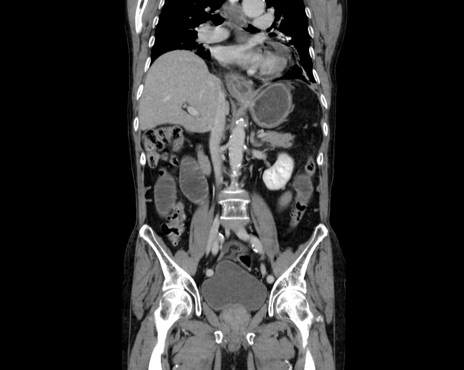

横断像

【症例】80歳代男性

【主訴】嘔吐

【現病歴】昨晩2回嘔吐あり、今朝になっても嘔吐あり。来院。

【既往歴】胃潰瘍

【身体所見】意識清明、BT 37.6℃、BP 166/95mmHg、HR 100bpm、SpO2 97%、腹部:平坦・軟、腸蠕動音聴取良好、圧痛なし。

【データ】WBC 21900、CRP 1.4